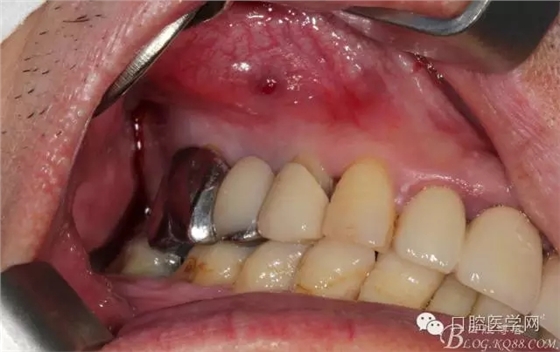

牙周治療以后過了段時間我們開始拔牙種牙,上圖是牙周治療以后開始種牙的口內(nèi)照片,效果還是有的。

簡單清理以后 (一般這種情況我是不太翻瓣的)這個患者我在清理13遠(yuǎn)中時候我發(fā)現(xiàn)有些肉芽而且超過了我的預(yù)期的量,我開始不太淡定了 。 我在想牙周科同事是不是知道我要拔牙,沒有在14 16 牙位用洪荒之力刮治啊。結(jié)果我翻瓣一點點去檢驗了下牙周科刮治的效果,那么結(jié)果是非常好,沒啥太多的肉芽,不翻瓣完全可以刮干凈,看來我得信任我的同事啊,牙周科非常給力。13牙位遠(yuǎn)中的肉芽估計的確不好刮掉,所以留給我刮了吧。

軟組織簡單處理以后 簡單縫合 植體三維空間非常理想